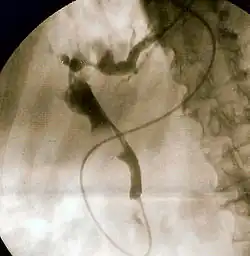

Il est posé à partir de la recherche de symptômes et signes de lésions (nodulaires ou diffuses) du foie ou d'autres maladies hépatiques, qui passe par l'interrogatoire du patient, de l'auscultation/palpation, de l'examen des bilans urinaires ou sanguins de divers test ou moyens d'investigation (de l'échographie au scanner en passant par la radiographie ou la biopsie).